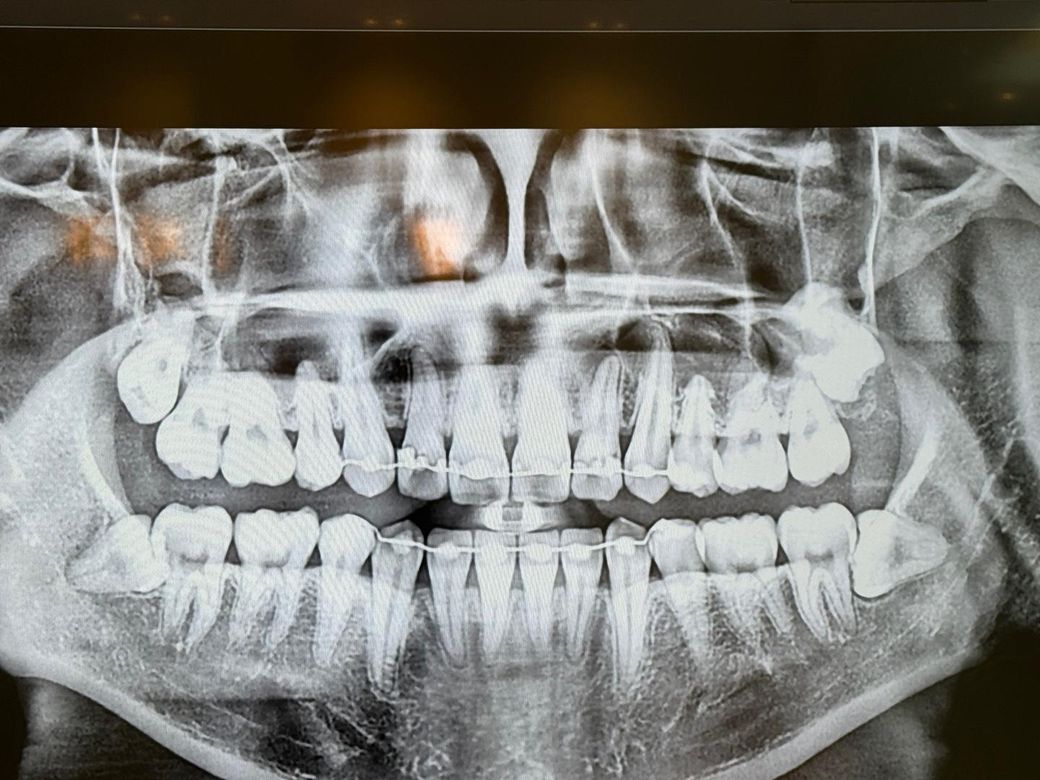

치과의사분들 파노라마 사진 해석부탁드립니다

사진상 앞니 오른쪽 뿌리끝에 작은 염증이 있다고 합니다

사진은 24년1월 24년 12월 25년 5월 순입니다

염증이 커지는 상황일까요?

아픈곳이나 시린곳은 없습니다 치료해야된다고 보시나요

엑스레이 상으로는 크게 염증이 커지거나 그렇진 않은거 같습니다. 증상이 없다면 정기적으로 치과를 다니시면서 관리를 받으시면될것같습니다.

사진상으로는 염증이 명백히 보이지만 증상이 없다면 일단 지켜보는 것도 괜찮을 것 같습니다.

파노라마 사진상으로 측은단 부위에 병소가 보이고 있습니다. 정확한 확인을 위해서는 CT 촬영을 해보는 것이 좋을 것으로 생각되며 치근단 질환이 생겼다는 것은 근관 내가 이미 감염이 되었다는 것이기 때문에 치근단 질환이 있다면 신경 치료를 해줘야 합니다. 그렇지 않다면 주변에 있는 치조골이 손상되어 나중에는 치아를 손실 할 수도 있습니다.